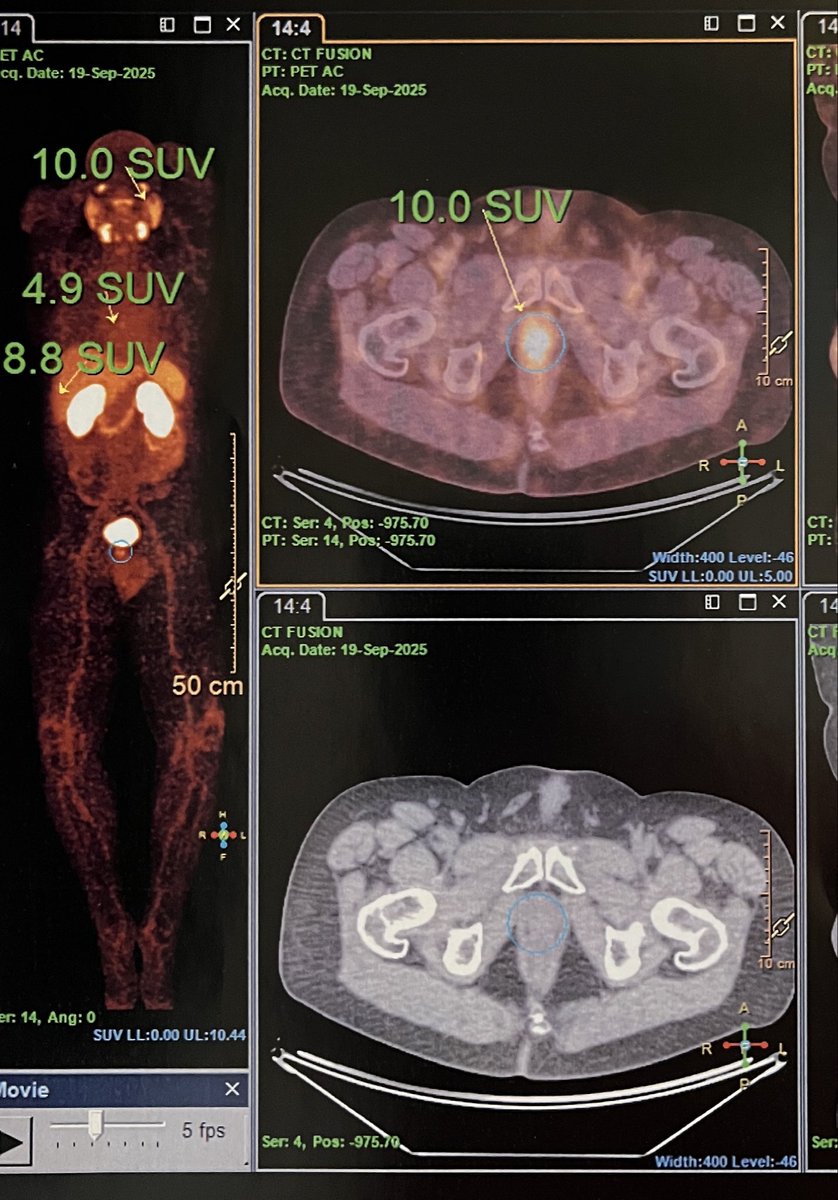

@AzadOncology asking the question- do all patients need six cycles of Lu-PSMA in #PSMAaddition? Showing a nice example of complete response after two cycles on #UpFrontPSMA